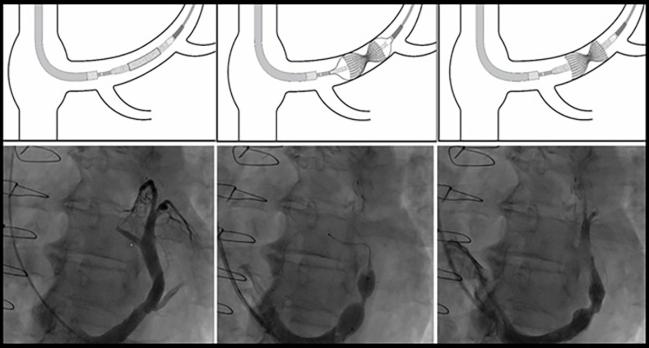

Photo Credit: Adapted from Verheye S. The coronary sinus reducer. Presented at: TCT 2023. San Francisco, CA.

There are limited therapeutic options for patients with refractory angina despite maximal antianginal treatment, and the CSR has emerged as an option for symptom relief. “This hourglass-shaped, stainless-steel mesh is percutaneously implanted to create a controlled narrowing in the coronary sinus, hypothesized to redistribute blood flow from well-perfused areas to ischemic myocardial regions,” the investigators say.